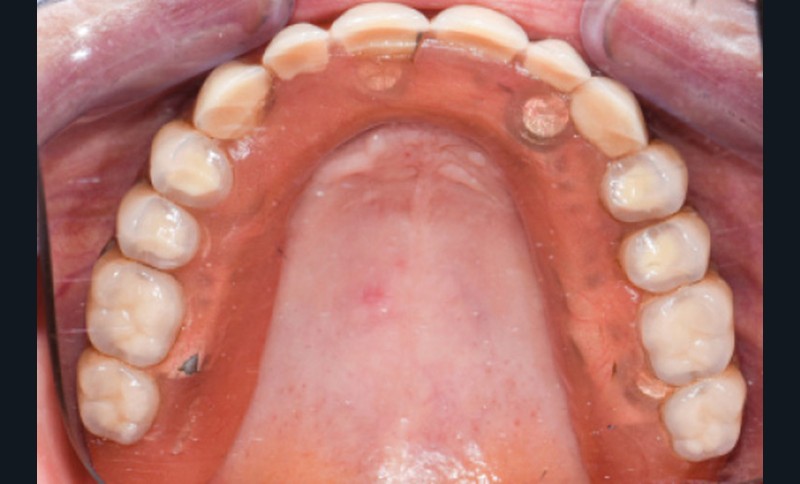

Une patiente de 65 ans consulte pour la perte d’adaptation de sa PACSI lors de la mastication. L’interrogatoire médical ne révèle aucune pathologie ni traitement médicamenteux. La patiente mentionne ne pas fumer et est sérieuse sur le plan prophylactique. Cependant, depuis quelque temps, elle se plaint d’une difficulté à mastiquer associée à une mobilité de sa prothèse et une usure des dents prothétiques (fig. 1a à e).

Une réhabilitation par PACSI maxillaire a été réalisée dix ans auparavant sur 5 implants en place de 13, 12, 21 et sur 24 et 26 (fig. 2a et b). Dans le cadre du plan de traitement initial, 6 implants avaient été indiqués. L’un d’entre eux, en position distale dans le secteur I, n’a jamais été ostéointégré. La patiente ne souhaitant plus de chirurgie, il avait donc été décidé de réaliser une prothèse sur 5 implants. La barre est directement connectée aux implants. À la mandibule, la patiente présente également une PACSI sur 2 implants associés à 2 piliers Locator®.